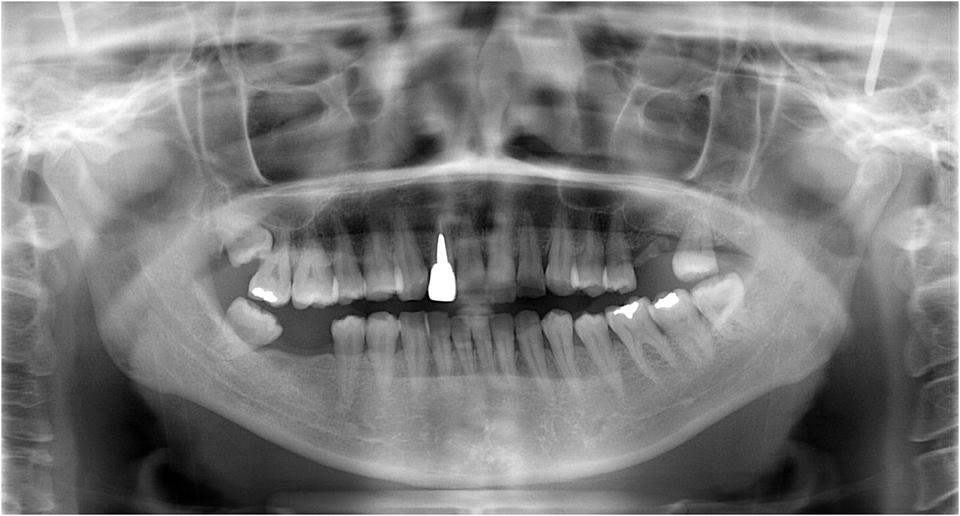

ある方の例です。親不知が痛くなってきました。一見問題ないようです。でも歯周病を常に治療している優れた歯科医師ならば、乾燥させてみた歯茎の色の変化で殆ど歯周病罹患部を指摘できるそうです。

検査をすれば恐ろしいほどの状態だといえるのです。10年後は虫歯と歯周病で残っている歯は何本なのか心配になってきました。